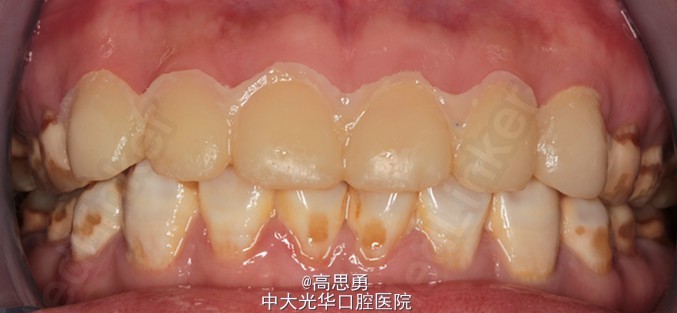

诊断:氟斑牙(着色型、中度) 患者意愿:患者希望尽快解决全口牙颜色改变的问题,不希望接受效果不明确、复诊次数多、维持时间短的治疗方案,可以接受费用较高的治疗方案,希望达到牙齿永久的形态、排列、颜色的尽可能完美的效果,但要求尽量少损伤牙体结构。下颌牙暂时不修复。 治疗方案:全瓷贴面修复,改善前牙美观。